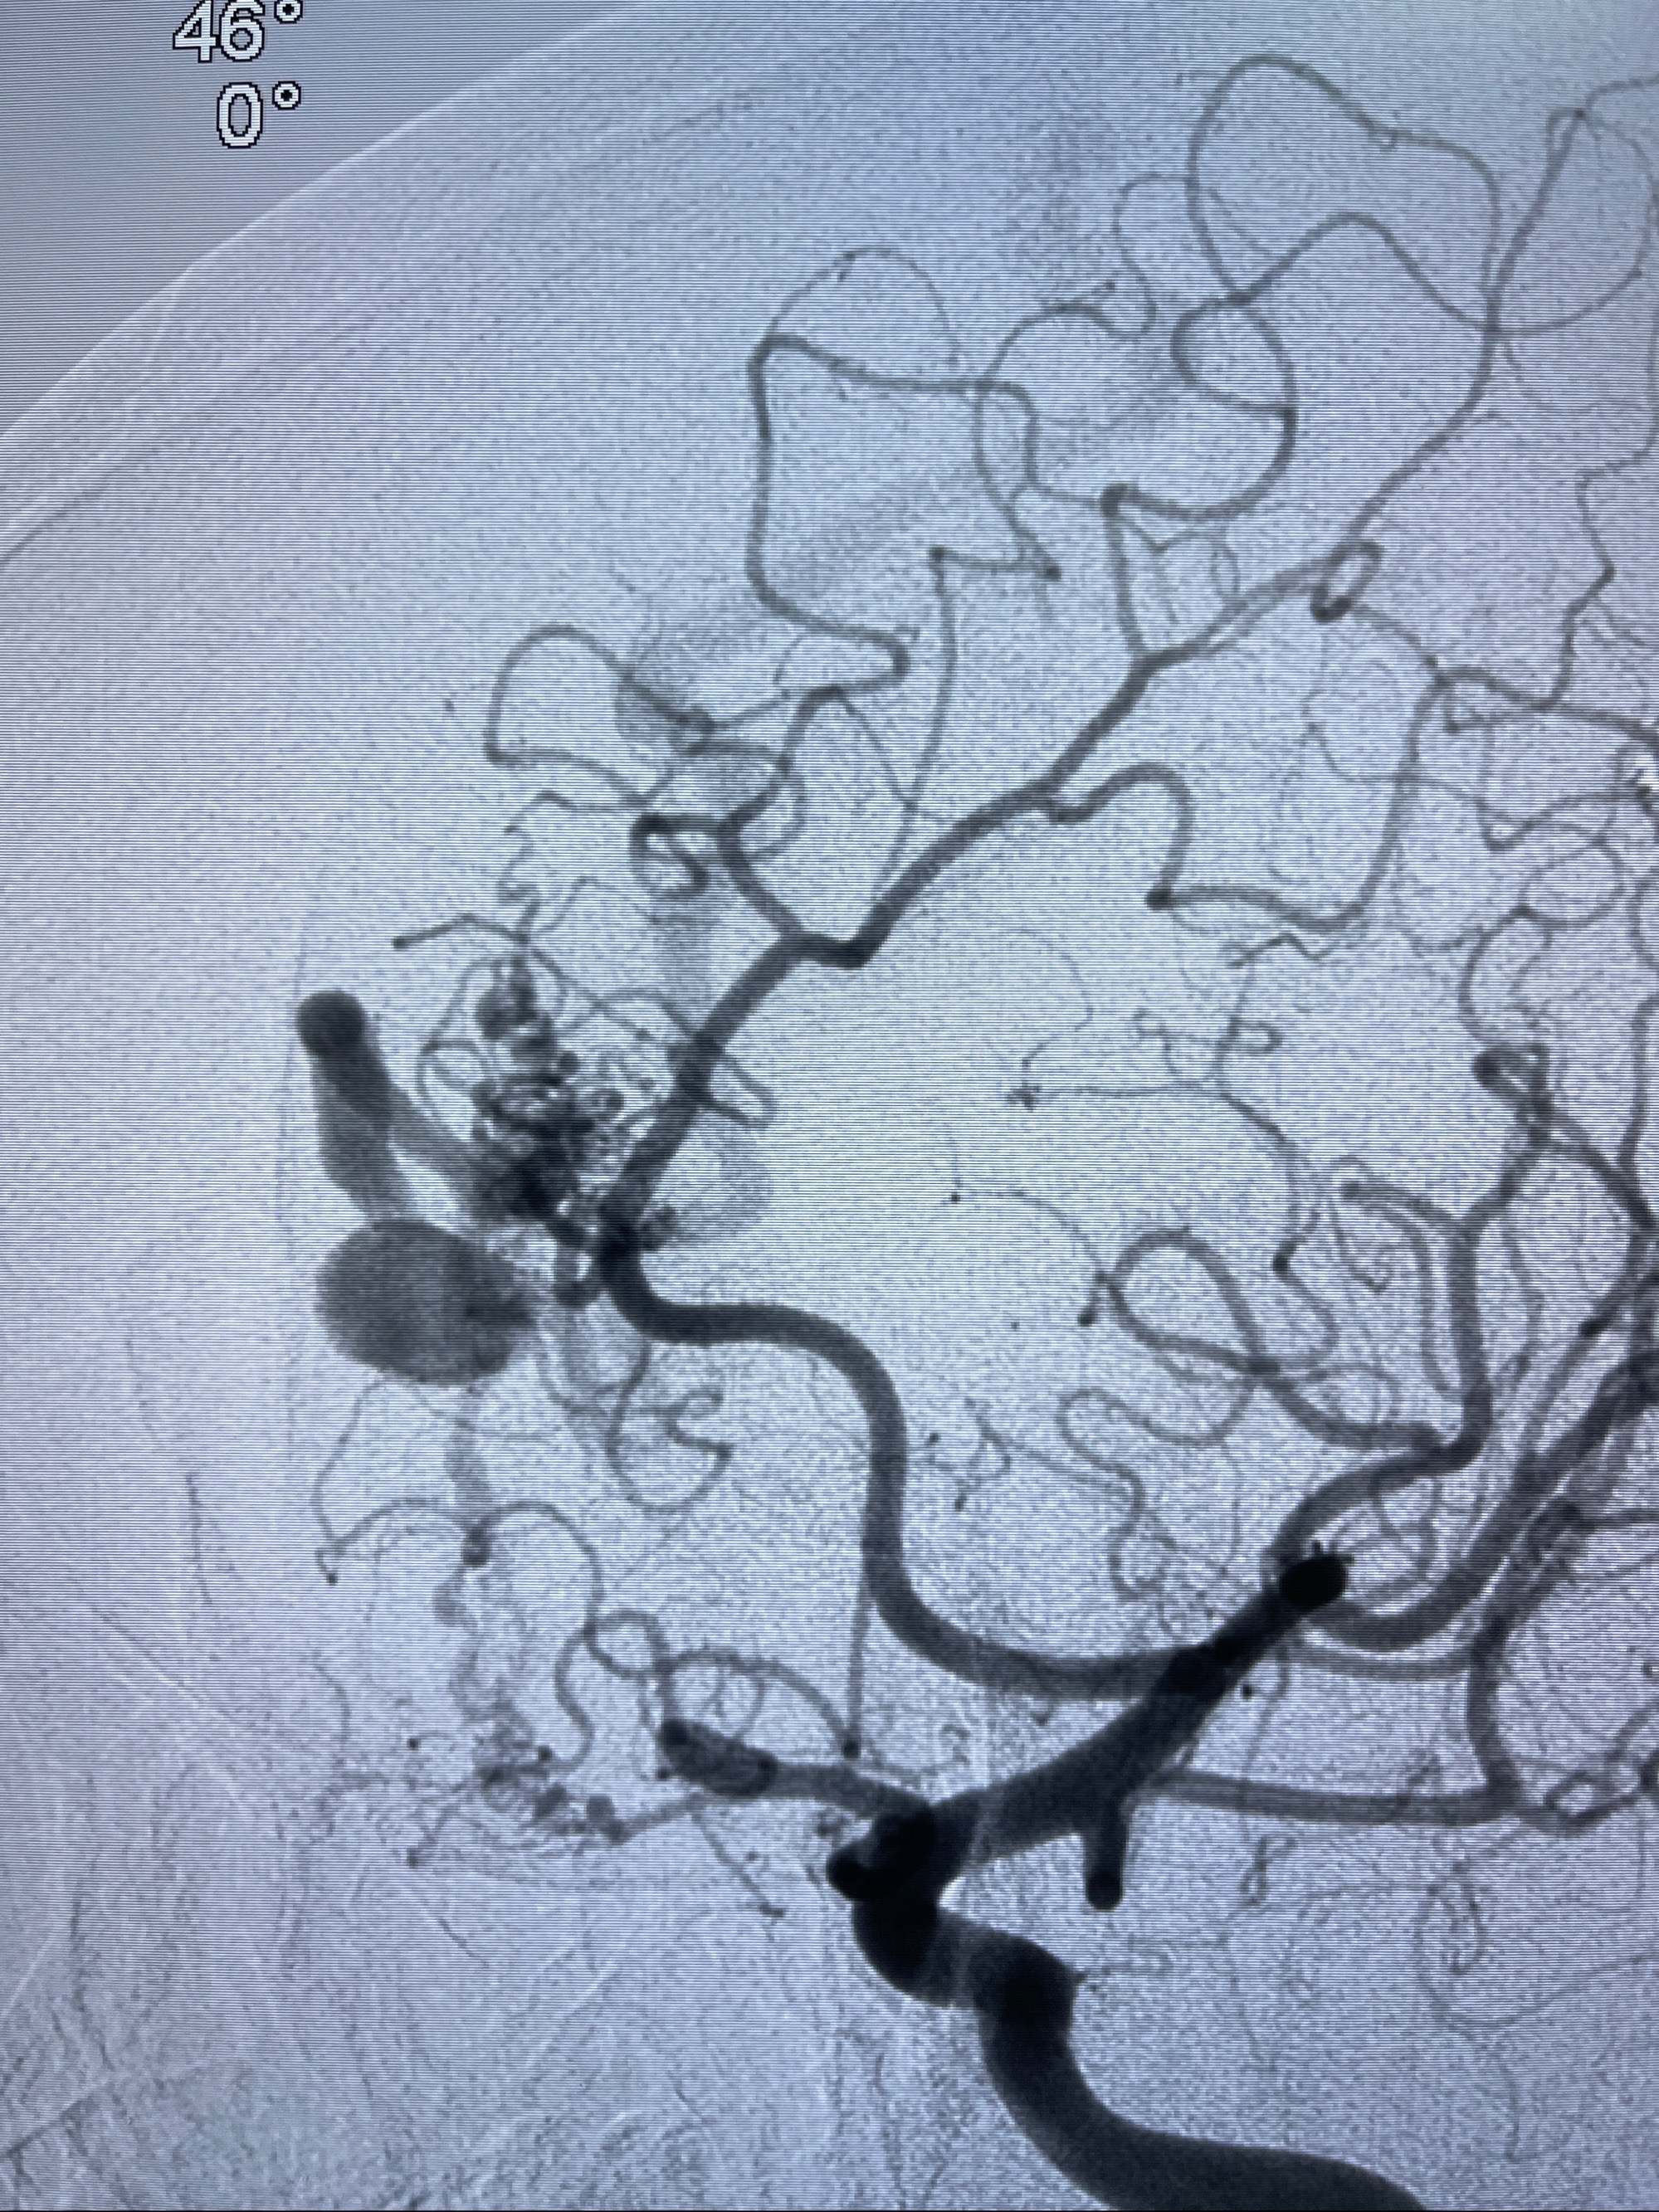

2023-09-13全脑血管造影:前颅底硬脑膜动静脉瘘,供血动脉为双侧胼周动脉、眼动脉脑膜支,静脉向上矢状窦方向引流

治疗策略:

- 外科手术?

- 介入干预:静脉途径栓塞or动脉途径填塞?